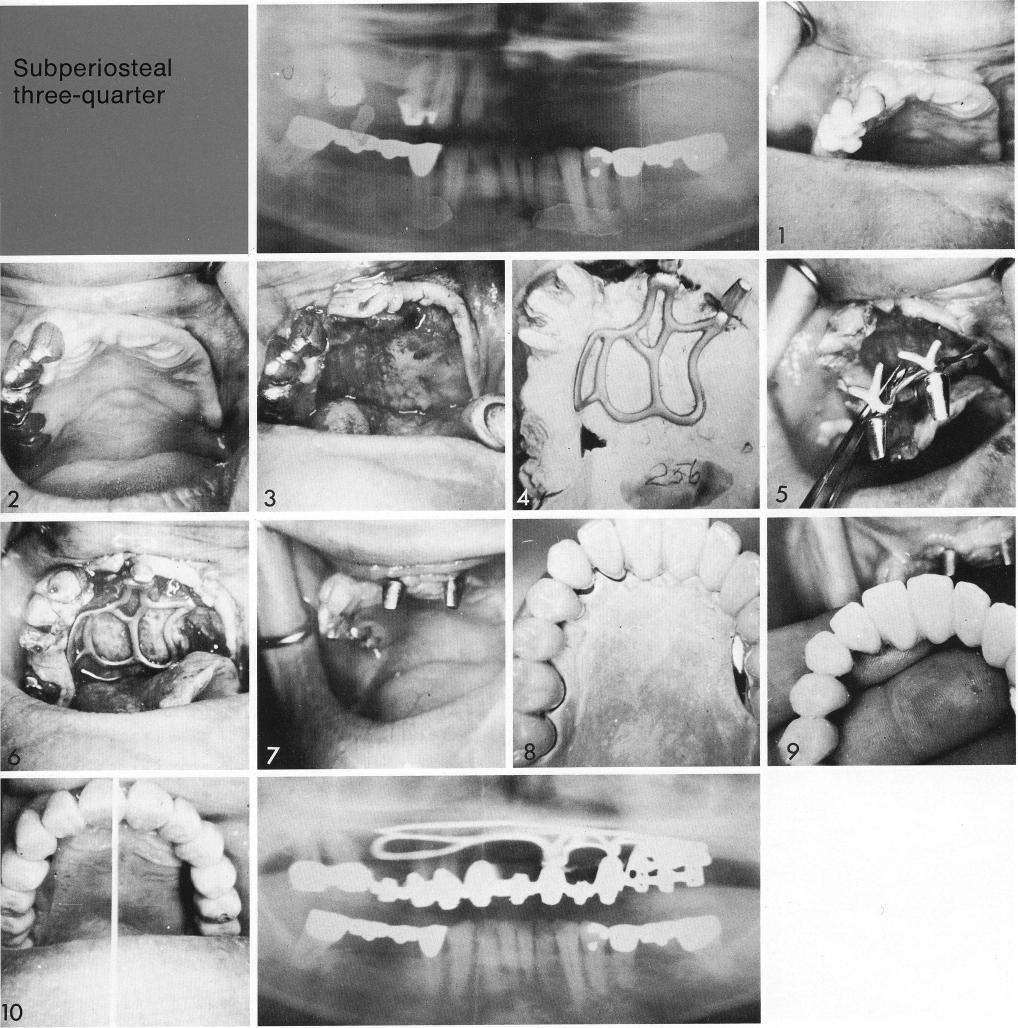

The modified toroplant idea was particularly promising when stable natural teeth were included (1,2). The toroplant was designed with its protruding posts (3) to balance the natural teeth (4,5) and brace against the bone investing the teeth (6). Thus balanced bilateral abutments (7) could support a natural looking, palateless, full-arch restoration (8-10).

1 Modified toroplant used when stable maxillary natural teeth included